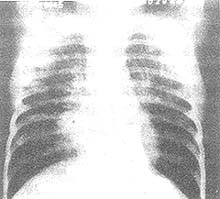

其他輔助檢查:CAP 嚴重程度影響肺炎吸收速度。重症CAP 在X 線上的吸收一般需要10 周左右時間,而輕中症CAP 吸收時間為3~4 周。不同病原體肺炎吸收速度和臨床改善可以有很大差異。肺炎鏈球菌肺炎在無合併症者其臨床改善頗快。據研究發熱消退大多很迅速,持續超過20 天者大約僅有6%;1 個月仍有異常體徵者僅8%,主要見於病情嚴重和多肺葉病變患者。但是,X 線上吸收相對緩慢,病程1 周X 線隨訪有20%~30%患者沒有吸收,而且還常可以見初期的惡化。總之,肺炎的自然病程或者X 線的消散時間可能呈現一個常態分配曲線,並受到多種因素影響。